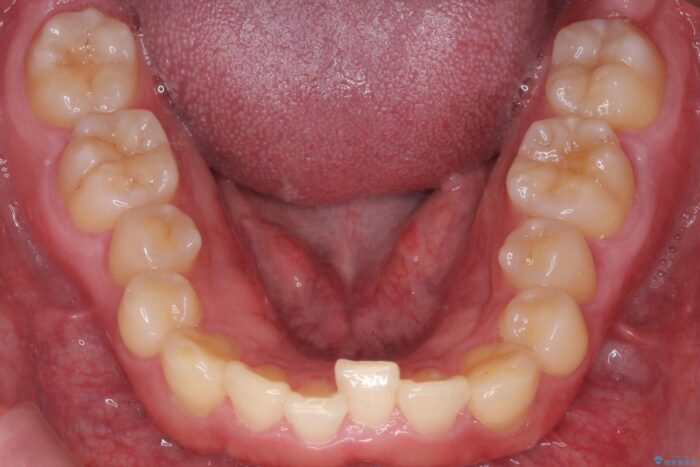

下の歯のがたつきが気になるとご来院されました。

部分矯正を行いシザーバイトを改善した後、インビザラインで歯列を整えました。

歯のがたつきが改善され大変お喜びいただけました。